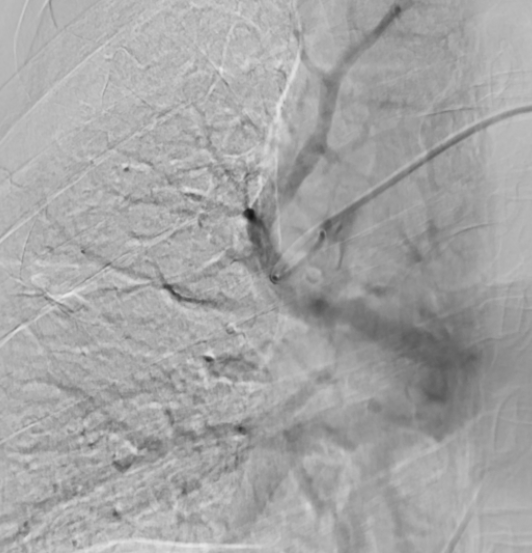

A 66-year-old woman experienced progressive lower limb swelling for 10 days, followed by sudden chest pain, chest tightness, and shortness of breath for 2 days. She was diagnosed with pulmonary embolism at another hospital but showed poor response to medication, with blood oxygen saturation around 80%. After being admitted to our department, emergency interventional thrombectomy and pulmonary artery thrombolysis were performed, raising her blood oxygen saturation to 98% and significantly relieving her chest pain symptoms.

Pre-Surgery

After Thrombus Suction